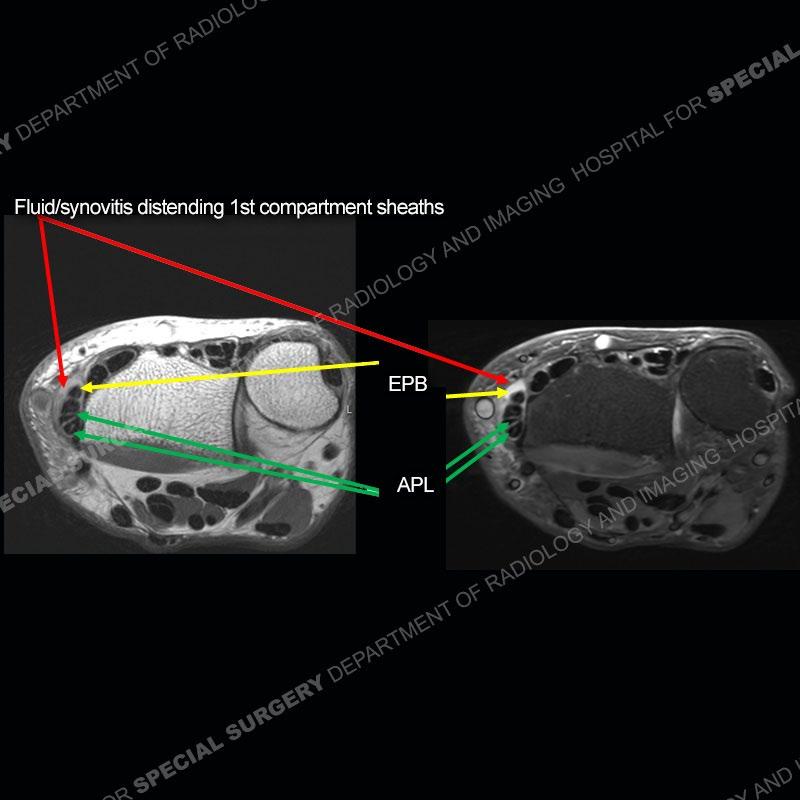

The radiographs in this case are not particularly contributory. The MRI demonstrates tenosynovitis of the first extensor compartment manifest by fluid/synovitis distention of the tendon sheaths. Multiple tendon slips are present of the abductor pollicis longus (APL) and with severe tendinosis seen of one of the tendon slips. Other areas of slightly increased signal and tendinosis are present of the components of the APL. Noted is a somewhat prominent septum separating the more dorsal extensor pollicis brevis (EPB) from the APL.

There can also be a partial or complete septum between the APL and EPB. This can particularly come into play with injections and positioning the needle into both sub-compartments to ensure that both tendons are bathed in the injectate.